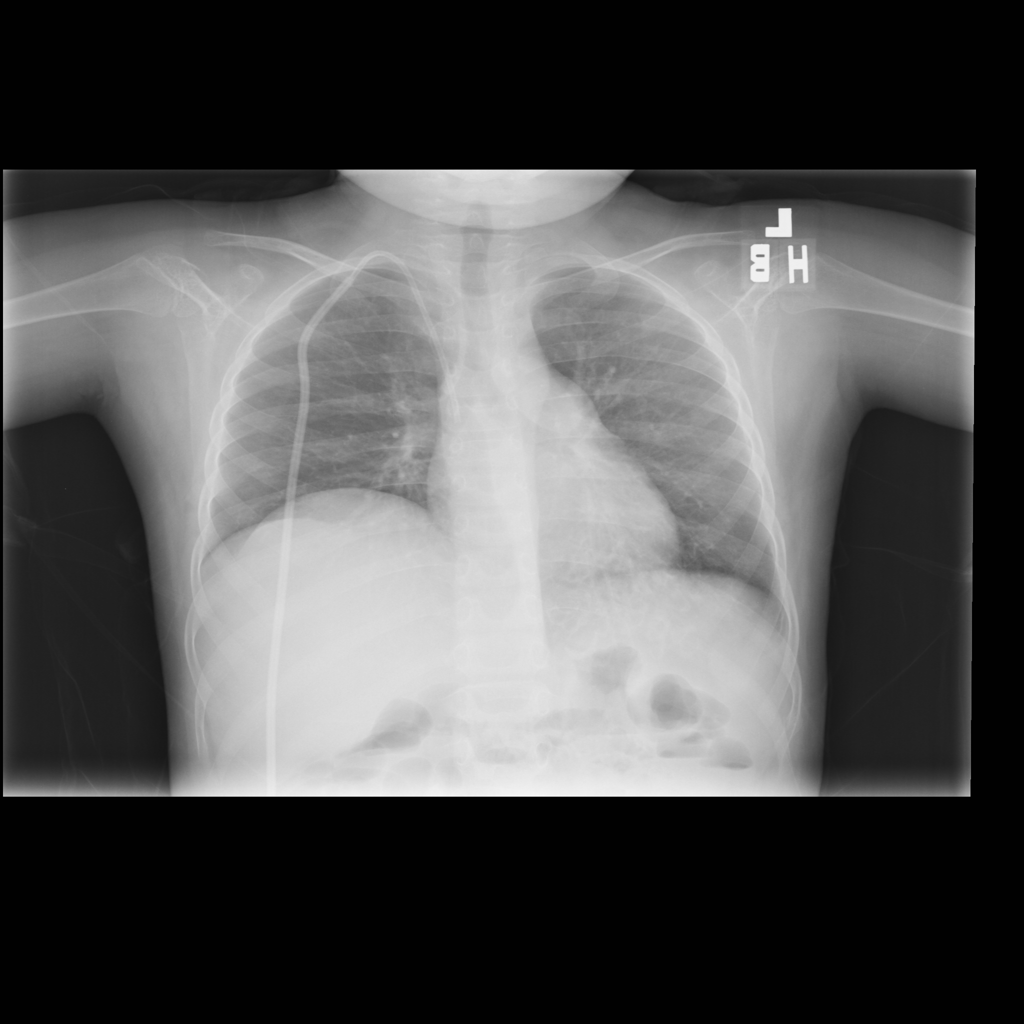

PAT-A1E2 · IMG-001Pneumonia

PAT-A1E2 · IMG-001

AP